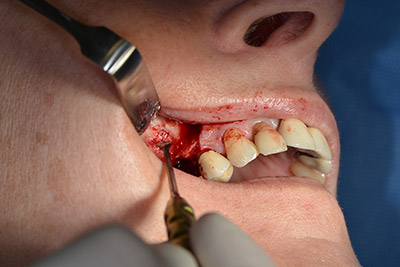

The fenestration was prepared at 35,000 rpm and then the nasal mucosa were prepared in the cranial direction (Fig. 13 to 14).

The implant was then placed and the bone built up. In this case, because of the size of the augmentation region, autologous bone chips, harvested with an osseous trap as drilling chips from implantation 16 and fenestration 14, were mixed with bone replacement material.